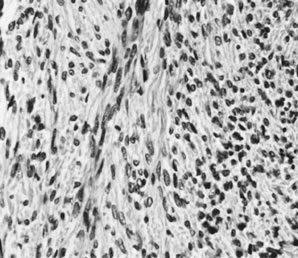

Ovarian fibromas occur at an average age of 48 years; fewer than 10% are encountered in females younger than the age of 30 years. These tumors are solid and have a fat, chalky-white, trabeculated appearance on their sectioned surfaces (Fig. 5). They are bilateral in approximately 10% of the cases.13 Microscopic examination shows intersecting fascicles of spindle cells producing collagen (Fig. 6); a storiform or pinwheel pattern is occasionally present. Hyaline plaques and foci of calcification are sometimes encountered, with calcification occurring, particularly in the bilateral tumors that are found in young women with the basal cell nevus (Gorlin's) syndrome.14 Intercellular edema is often present; a marked degree of edema has been correlated with the presence of ascites, which accompanies 40% of fibromas over 10 cm in diameter and with Meigs' syndrome (ascites and hydrothorax relieved by the removal of a benign ovarian tumor with fibromatous features), which occurs in fewer than 1% of the cases.15 Cellular fibromas with minor mitotic activity may recur, especially if they are found to be ruptured or adherent at the time of operation; even in the absence of rupture or adhesion, cellular fibromas occasionally recur many years after their removal.16 The rare fibrosarcoma is characterized by significant nuclear atypicality and mitotic activity that is generally greater on the average than three per 10 high-power fields; these tumors are highly malignant.

Fig. 6. Fibroma (magnification, ×325).(Serov SF, Scully RE, Sobin LH: Histological Typing of Ovarian Tumours. Geneva, World Health Organization, 1973.)